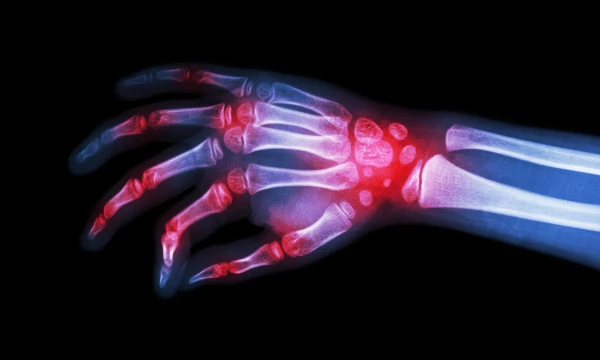

La esclerodermia es una enfermedad autoinmune que afecta principalmente a la piel y a los vasos sanguíneos, por lo que puede afectar a otros órganos, como el pulmón, corazón, riñón, entre otros. El compromiso de la piel se caracteriza por la disminución progresiva de la elasticidad de la piel, con sensación de endurecimiento de la piel en dichas localizaciones. Se presenta predominantemente en mujeres entre los 30 y 50 años, aunque puede manifestarse desde la infancia.

Además, en ambos casos se puede presentar Fenómeno de Raynaud (cambios de coloración de la piel, especialmente de las manos, con la exposición a cambios de temperatura, más notorios con el frío); compromiso del esófago caracterizado por síntomas de reflujo gastroesofágico; alteración de la función pulmonar (dificultad respiratoria, fatiga); así como manifestaciones en otros órganos como riñón, sistema nervioso, etc.

Como vemos los síntomas son muy variados, y pueden pasar varios años antes de hacer el diagnóstico, porque la progresión de la enfermedad puede ser lenta. Si presenta síntomas persistentes o que se incrementan como el Fenómeno de Raynaud, reflujo severo, cambios en la elasticidad de la piel de las manos, cara, cuello y tórax, aparición de lesiones de consistencia dura en los pulpejos de los dedos, que cuando las extraen contienen calcio (calcinosis), dificultad respiratoria, es importante que consulte para que lo estudien y se le inicie tratamiento de acuerdo al compromiso que tenga, ya que no existe un tratamiento que le sea de utilidad a todos los pacientes. También tenga en cuenta que son muchos los profesionales de la salud involucrados en el manejo ya que por tener manifestaciones de diversos sistemas puede requerir la valoración de Dermatología, Reumatología, Gastroenterología, Neumología, Cardiología, Nefrología, Medicina Física y Rehabilitación, Psiquiatría, Terapia Física y Ocupacional, Psicología, Nutrición, entre otros.